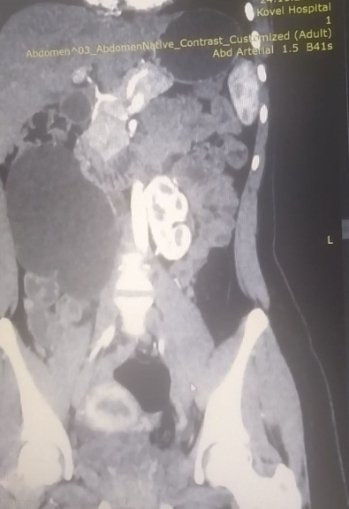

17-річна пацієнтка мала вроджену ваду сечовидільної системи - підковоподібну нирку (зрощення двох нирок). Стан її здоров’я погіршувався упродовж багатьох років, аж поки права половина підковоподібної нирки перестала функціонувати.

Лікарі діагностували термінальний гідронефроз із наслідками, гідронефротичну трансформацію правої половини підковоподібної нирки, вторинну артеріальну гіпертензію.